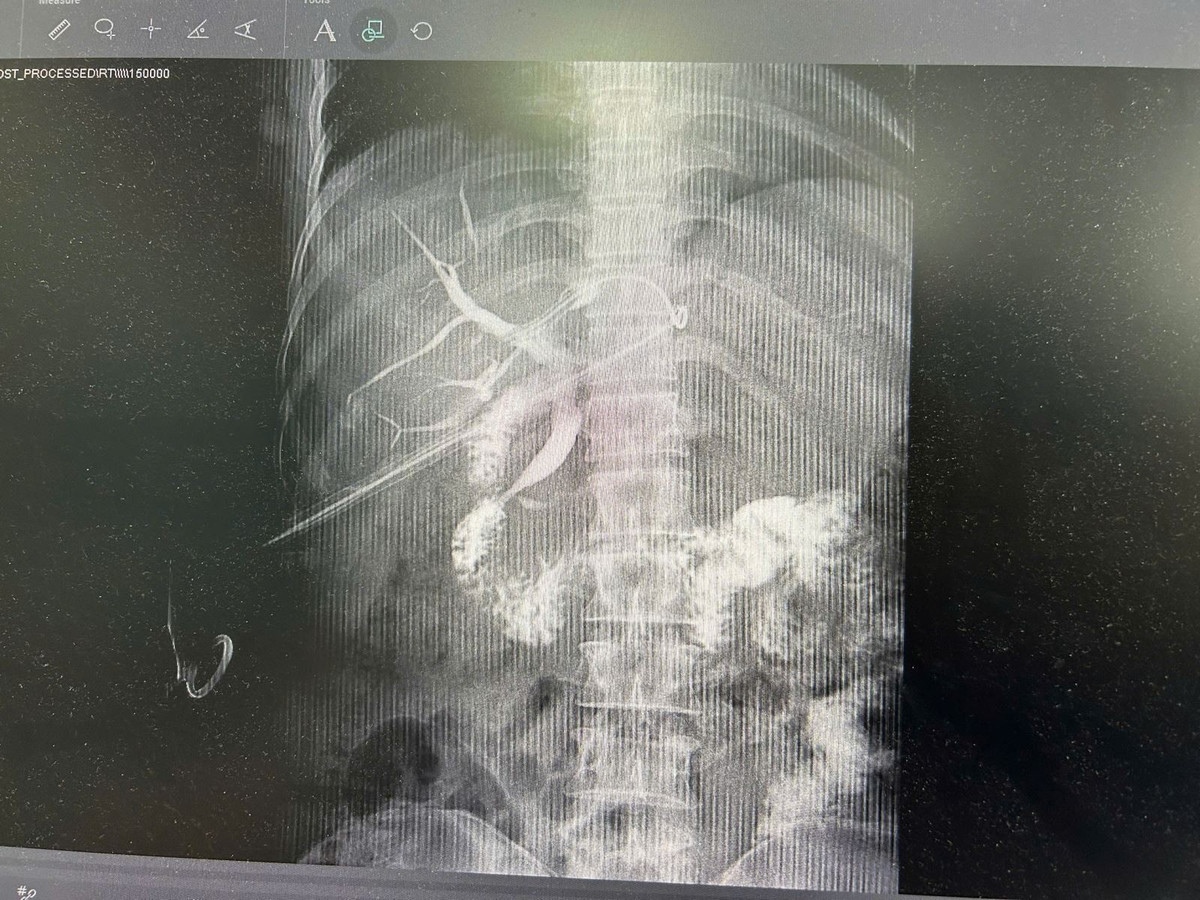

ong-mat.jpg

Hình ảnh ống mật đã được làm sạch sỏi sau phẫu thuật trên bệnh nhân N.T.L 45 tuổi - Ảnh BVCC